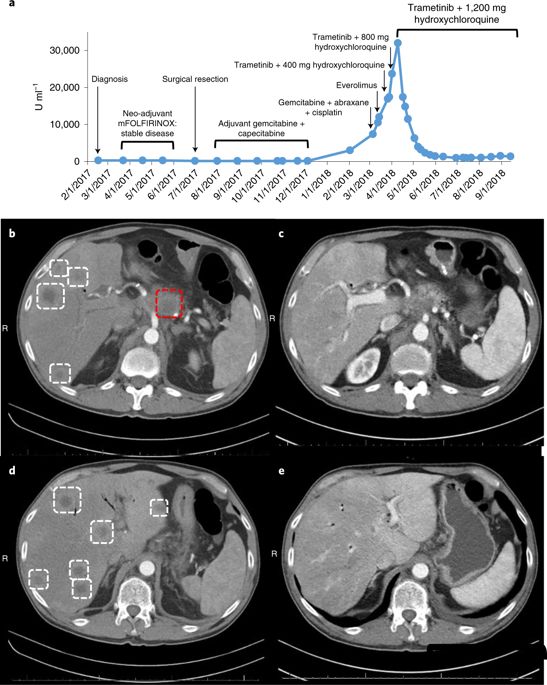

这种联合疗法的效果在一位晚期胰腺癌患者身上同样得到了证实,这位患者在手术后,接受了几次化疗,但不幸的是癌症复发并转移了,目前已经没有很好的治疗方案,

这名患者接受了 trametinib和hydroxychloroquine治疗,令患者和医生震惊的是,奇迹出现了,2个月内,患者的胰腺癌标志物CA 19-9的血液水平下降了95%。4个月后,他体内的癌症数量减少了50%。

用曲美替尼加羟氯喹(T / HCQ)治疗胰腺癌患者导致肿瘤标志物癌抗原19-9(CA19-9)和总体肿瘤负荷减少。